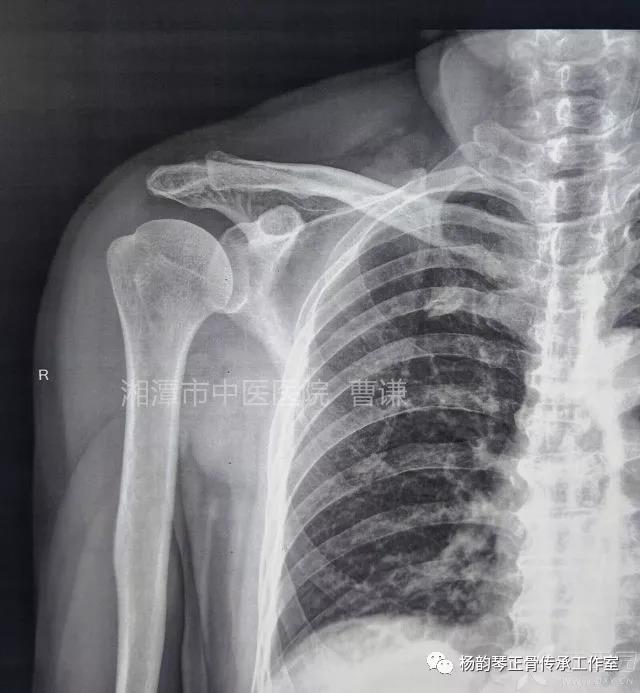

简要病史:骑摩托车跌倒致左肩部肿痛,活动受限,就诊于当地医院,拍片及磁共振检查后诊断为肩袖损伤及肩关节半脱位,予以悬吊固定,因症状缓解不明显就诊于我院。外院拍片情况如下:

应该说是一个典型的“灯泡征”影像,但是并未引起注意。

当地接诊医生应该说还是很负责的,同时拍了健侧片对比:

影像科报告,骨科医生光看报告行吗?